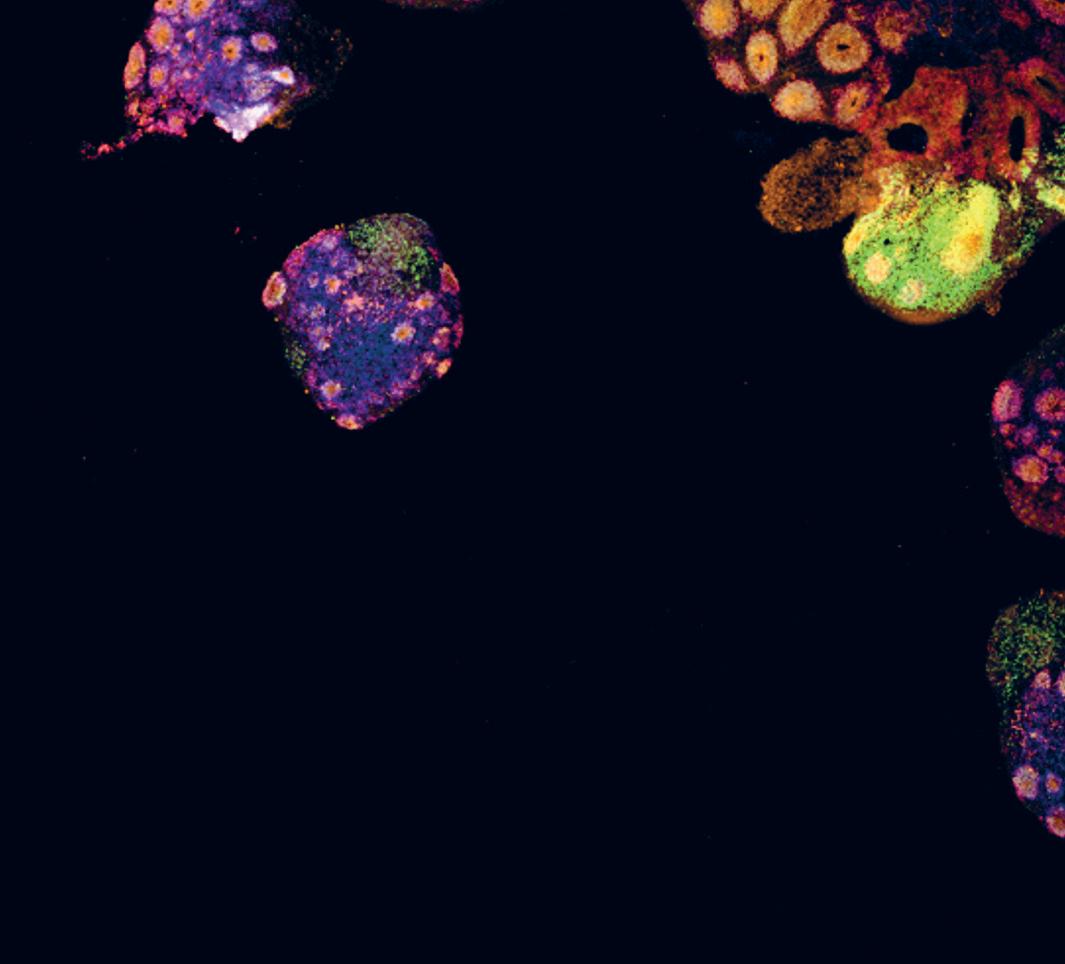

Dit blauwe beeld is een doorsnede van de hersenen van een fruitvlieg. We gebruiken die – en verschillende andere modelsystemen - om ziektes te onderzoeken zoals dementie en Parkinson.

This blue image is a cross-section of the brain of a fruit fly. We use that - and several other model systems - to study diseases such as dementia and Parkinson’s.

Leuven Brain Institute

We kennen allemaal de meest bekende symptomen van Parkinson: trillen, stijfheid en moeite met bewegen, maar Parkinson heeft veel andere symptomen. De precieze oorzaak is nog steeds onbekend. Wel hebben wetenschappers de voorbije jaren diverse gendefecten (mutaties) bij Parkinsonpatiënten beschreven. Verschillende daarvan, de zogenaamde Pink1- en Parkine-mutatie, verminderen de werking van “mitochondriën”. Dat zijn kleine energiecentrales in de cellen die ervoor zorgen dat ons lichaam goed functioneert. Als ze falen, sterven er hersencellen, met de bekende gevolgen.

In ons onderzoek gebruiken we de crispr-cas9-techniek om een stukje dna uit de fruitvlieg te verwijderen en te vervangen door de menselijke versie van een gen dat Parkinson veroorzaakt. In veel gevallen werkt het menselijke gen in de fruitvlieg op een gelijkaardige manier. Wanneer we het vliegen-pink1 gen vervangen door de zieke menselijke variant, dan krijgen de fruitvliegen problemen met hun mitochondriën: ze ondervinden problemen met het bewegen, slapen niet goed en krijgen last met hun reukzin.

We onderzoeken manieren om de effecten van de menselijke pink1-mutatie ongedaan te maken. We ontdekten zo dat het toedienen van extra vitamine k2 aan de zieke fruitvliegen ervoor zorgde dat hun energieproductie verbeterde, en ze weer konden vliegen, slapen en ruiken. Een bijzondere ontdekking, omdat het aangeeft dat vitamine k2 mogelijk de energieproductie in de hersencellen verbetert, én zo voorkomt dat ze beginnen af te sterven. Uiteindelijk zou zulk een behandeling kunnen helpen om de symptomen van de ziekte van Parkinson te verlichten bij patienten met die Pink1 mutatie.

We all know the most well-known symptoms of Parkinson’s: tremors, stiffness and difficulty moving, but Parkinson’s has many other symptoms. The exact cause is still unknown. However, in recent years scientists have described various gene defects (mutations) in Parkinson’s patients. Several of these, the so-called Pink1 and Parkin mutations, reduce the functioning of “mitochondria”. These are small power stations in the cells that ensure that our body functions properly. If they fail, brain cells die, with the well-known consequences.

In our research, we use the crispr-cas9 technique to remove a piece of dna from the fruit fly and replace it with the human version of a gene that causes Parkinson’s. In many cases, the human gene in the fruit fly works in a similar way. When we replace the fly pink1 gene with the diseased human variant, the fruit flies get problems with their mitochondria: they experience problems with movement, sleep poorly and have problems with their sense of smell.

We are investigating ways to reverse the effects of the human pink1 mutation. We found that giving the diseased fruit flies extra vitamin k2 improved their energy production, and allowed them to fly, sleep and smell again. This is a remarkable discovery, because it suggests that vitamin k2 may improve energy production in brain cells, and thus prevent them from starting to die. Ultimately, such a treatment could help to alleviate the symptoms of Parkinson’s disease in patients with the Pink1 mutation.